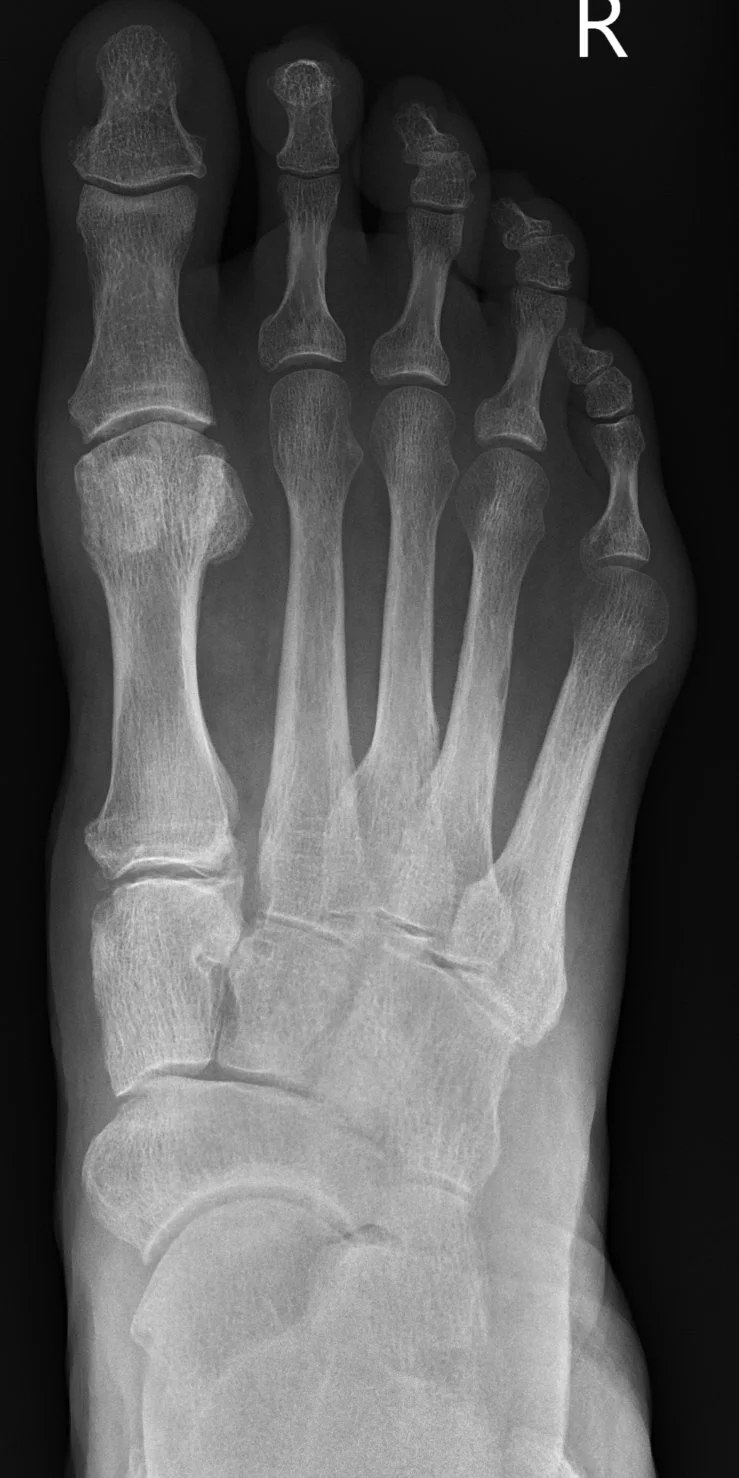

A bunionette , - also known as a Tailor’s bunion, small toe bunion, or bunion on the outside of the foot – is a bony lump that develops near the base of the little toe.

It happens when the bone on the outside of the foot (fifth metatarsal) becomes more prominent, either from natural foot shape, joint changes, or drifting of the toe.

bump on outer border of foot, often with the little toe / pinky curling or bending inwards